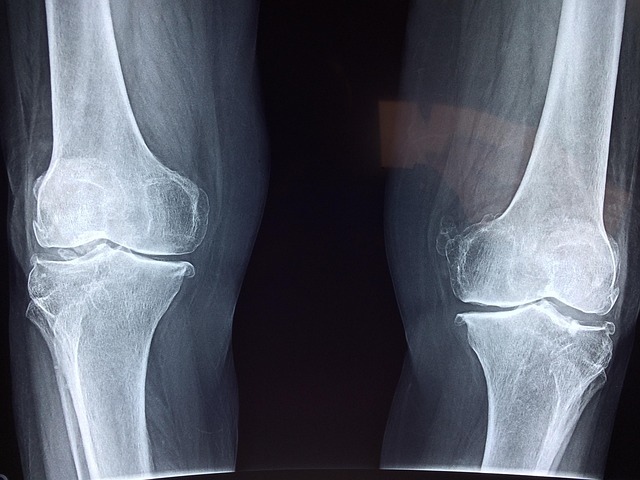

무릎이 자주 시큰거리시나요?

관절 통증은 움직이지 않아서 더 심해질 수 있습니다.

하루 10분, 누구나 따라 할 수 있는 관절 스트레칭 루틴으로 무릎과 다리 건강을 지키는 쉬운 방법을 알려드립니다.